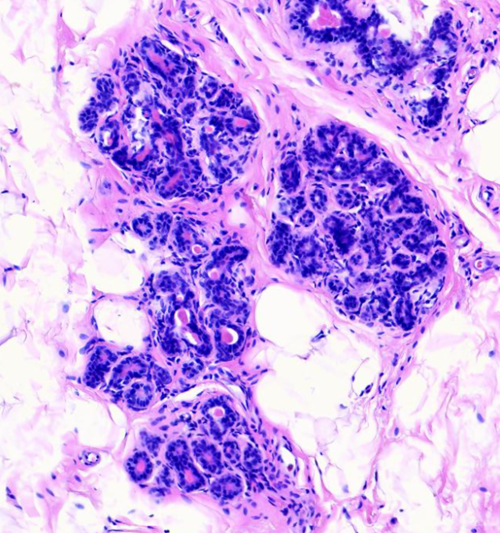

乳腺纤维腺瘤与周围正常腺体组织分界清楚,显微镜下可见其由良性的乳腺上皮和间质成分增生形成,细胞形态温和,无异型性。根据组织形态,可大致分为管内型和管周型,但分型对临床预后并无显著影响。该肿瘤经完整手术切除后,一般不会复发。

(图3:管周型纤维腺瘤)